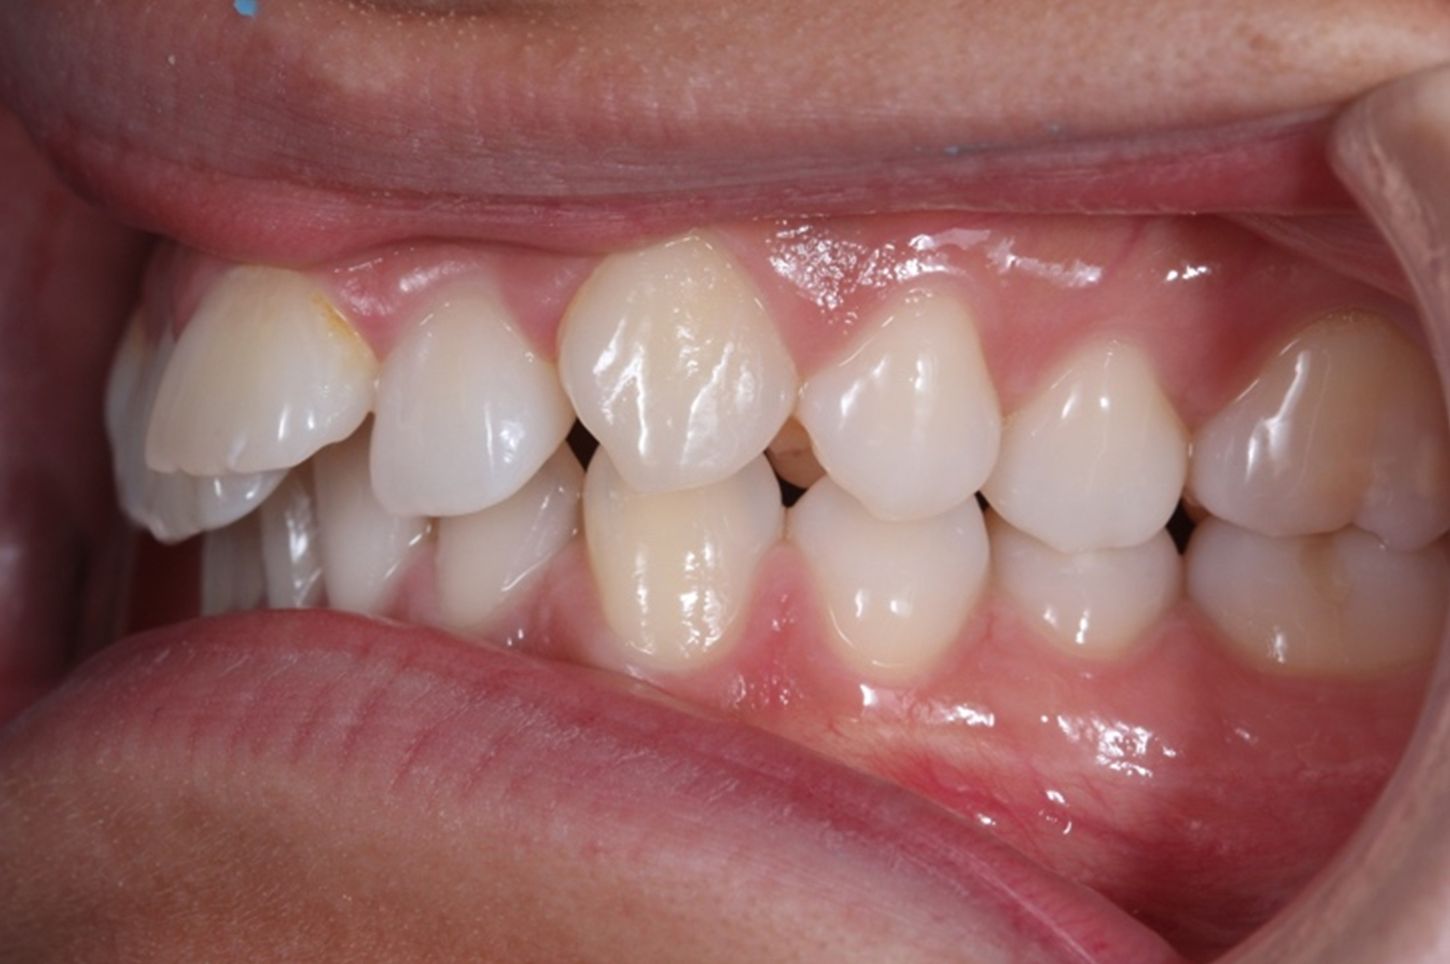

A continuación, mostramos el caso de una paciente adulta con clase II ósea y dentaria.

Con Ortodoncia Invisible, y gracias a la cooperación de la paciente, conseguimos este resultado y, lo más importante de todo, que la paciente sonría sin complejos.